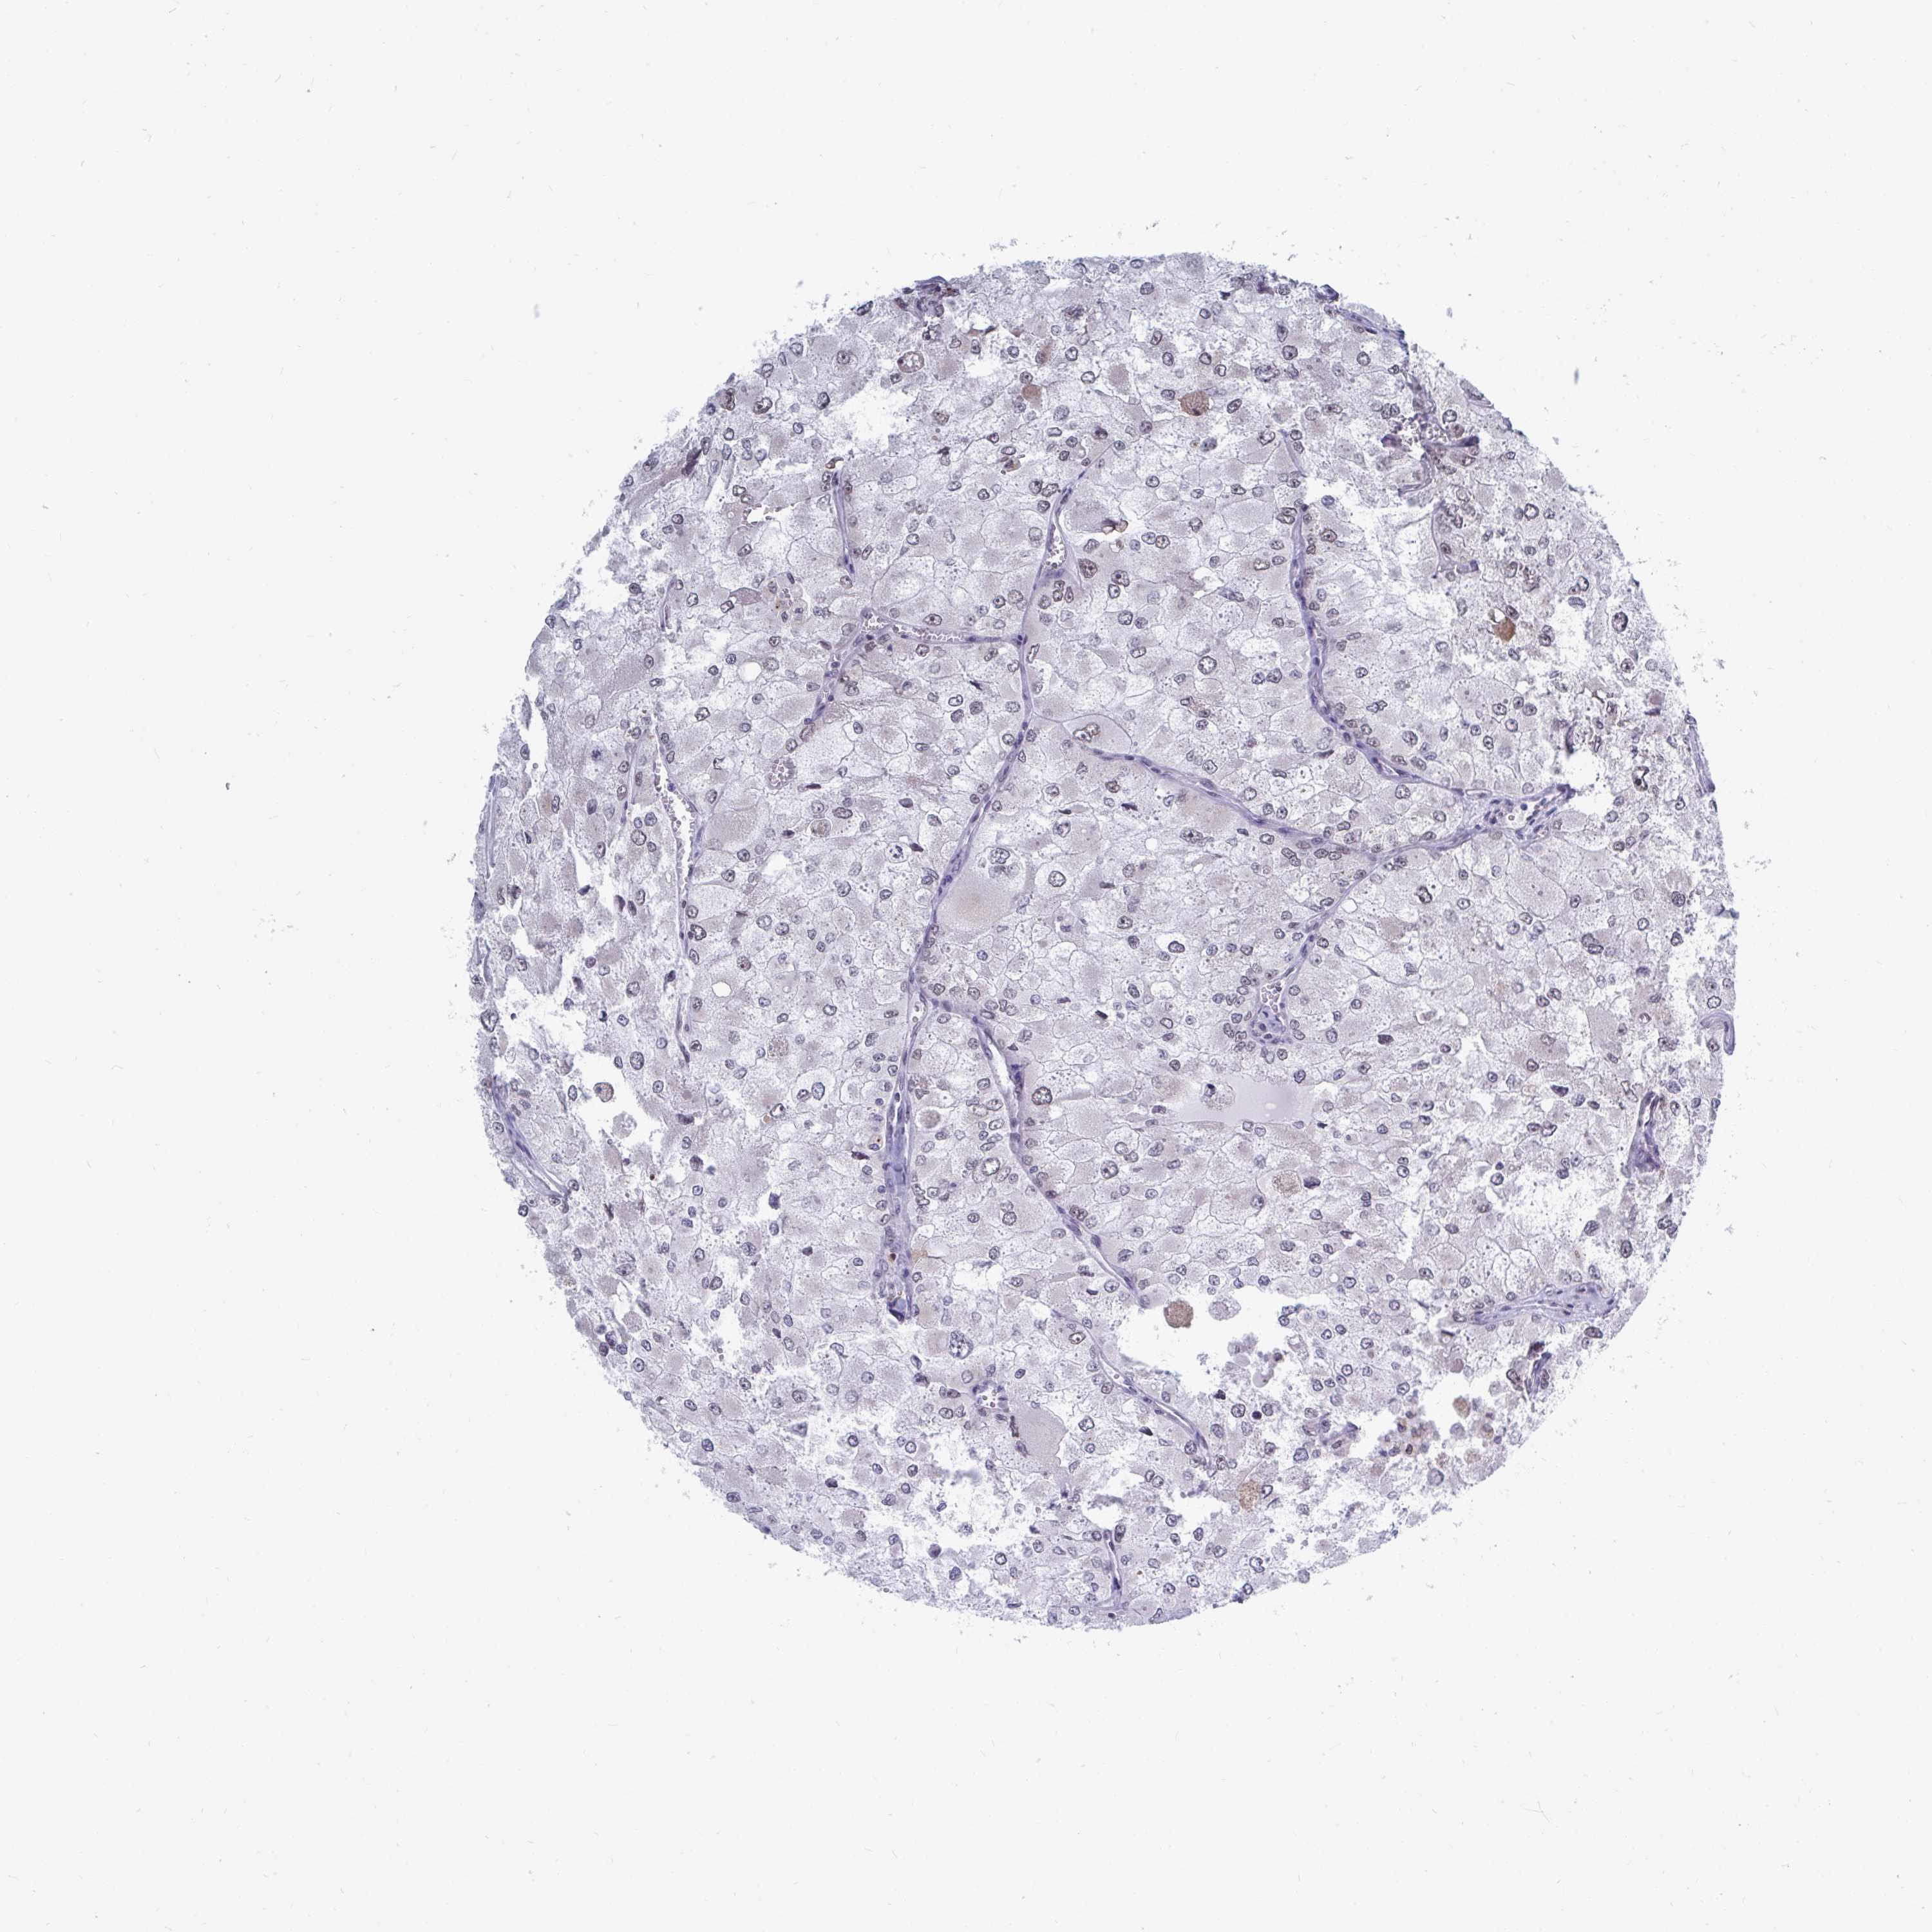

KIDNEY RENAL PAPILLARY CELL CARCINOMA (TCGA) - Interactive survival scatter ploti

The Survival Scatter plot shows the clinical status (i.e. dead or alive) for all individuals in the patient cohort, based on the same data that underlies the corresponding Kaplan-Meier plots. Patients that are alive at last time for follow-up are shown in blue and patients who have died during the study are shown in red.

The x-axis shows the expression levels (FPKM) of the investigated gene in the tumor tissue at the time of diagnosis. The y-axis shows the follow-up time after diagnosis (years). Both axes are complimented with kernel density curves demonstrating the data density over the axes. The top density plot shows the expression levels (FPKM) distribution among dead (red) and alive patients (blue). The right density plot shows the data density of the survived years of dead patients with high and low expression levels respectively, stratified using the cutoff indicated by the vertical dashed line through the Survival Scatter plot. This cutoff is automatically defined based on the FPKM cutoff that minimizes the p-score. The cutoff can be changed by dragging the vertical line or by entering a cutoff value in the square labeled "Current cut-off".

Under the Survival Scatter plot the p-score landscape (black curve; left axis) is shown together with dead median separation (red curve; right axis). Dead median separation is the difference in median mRNA expression between patients who have died with high and low expression, respectively. It is calculated as follows: median FPKM expression of dead patients with high expression - median FPKM expression of dead patients with low expression. This is intended to aid the user in visually exploring custom cutoffs and the associated p-scores and dead median separation.

Individual patient data is displayed and can be filtered by clicking on one or more of the category buttons on the top of the page. Categories describing expression level and patient information include: high, low, alive, dead, female, male and tumor stages. The scale of the x-axis can be toggled between linear and log-scale by clicking on the "x log" button. Mouse-over function shows TCGA ID, patient information and mRNA expression (FPKM) for each patient.

& Survival analysisi

Kaplan-Meier plots summarize results from analysis of correlation between mRNA expression level and patient survival. Patients were divided based on level of expression into one of the two groups "low" (under cut off) or "high" (over cut off). X-axis shows time for survival (years) and y-axis shows the probability of survival, where 1.0 corresponds to 100 percent.

TRIP12 is not prognostic in Kidney Renal Papillary Cell Carcinoma (TCGA)